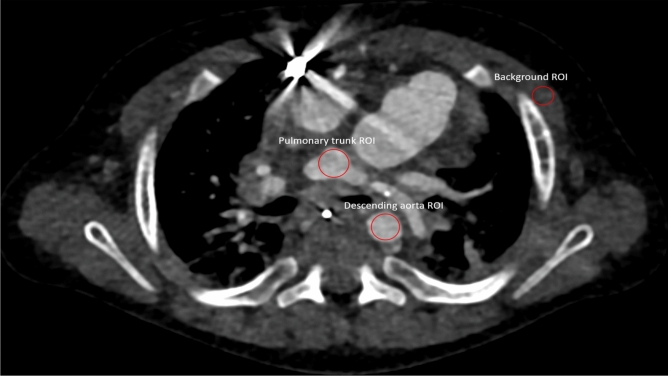

Additionally, SNR and contrast to noise ratio (CNR) were calculated as previously described (depicted in Eqs. 1 and 2)7. Regions of interest (ROI) were placed in the pulmonal trunk at the site of bifurcation, the descending aorta at the same height as the pulmonal trunk and muscle tissue at the same height as the pulmonal trunk. Pectoral muscles were used the background standard for the calculations. Due to the varying age and primary pathologies of the included patients, ROI size was scaled for each patient individually to include as much tissue as was available at the predetermined height as demonstrated in Fig. 1. All series were additionally rated to assess whether they sufficiently answered all clinical questions based on a numeric scale with 0 being non-diagnostic series, 1 some questions were answered, 2 most questions were answered, and 3 all questions were sufficiently answered.

Figure 1.

Region of interest (ROI) placement demonstrated in a 7-month-old male patient with hypoplastic left heart syndrome. Due to the varying anatomy of the included patients, ROI size was scaled individually for each patient to include as much reasonably possible without measuring adjacent tissues.